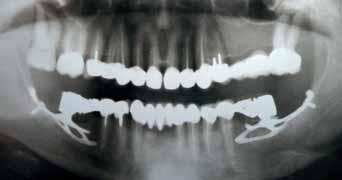

The Dental Panoramic Tomogram (DPT) confirmed the presence of all permanent teeth including the developing third molars (Figure 3). Root morphology appeared normal. The upper right central incisor had a root canal filling. The upper standard occlusal

radiograph revealed that the upper right central incisor had an adequate root filling with no periapical area. In the cephalometric assessment (Figure 4), the ANB value of 7° suggested a moderate Class II skeletal pattern. The vertical proportions were within normal values. The upper incisors were proclined at 122° and the lower incisors were of average inclination at 94°. The interincisal angle was reduced at 119°. The lower incisor to APo and the lower lip to E line were within normal limits.